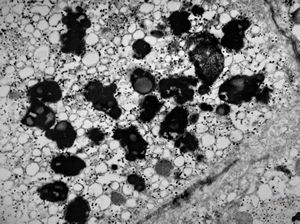

M,2y. | dense mitochondrial inclusions - clinically susp. Zellweger syndrome